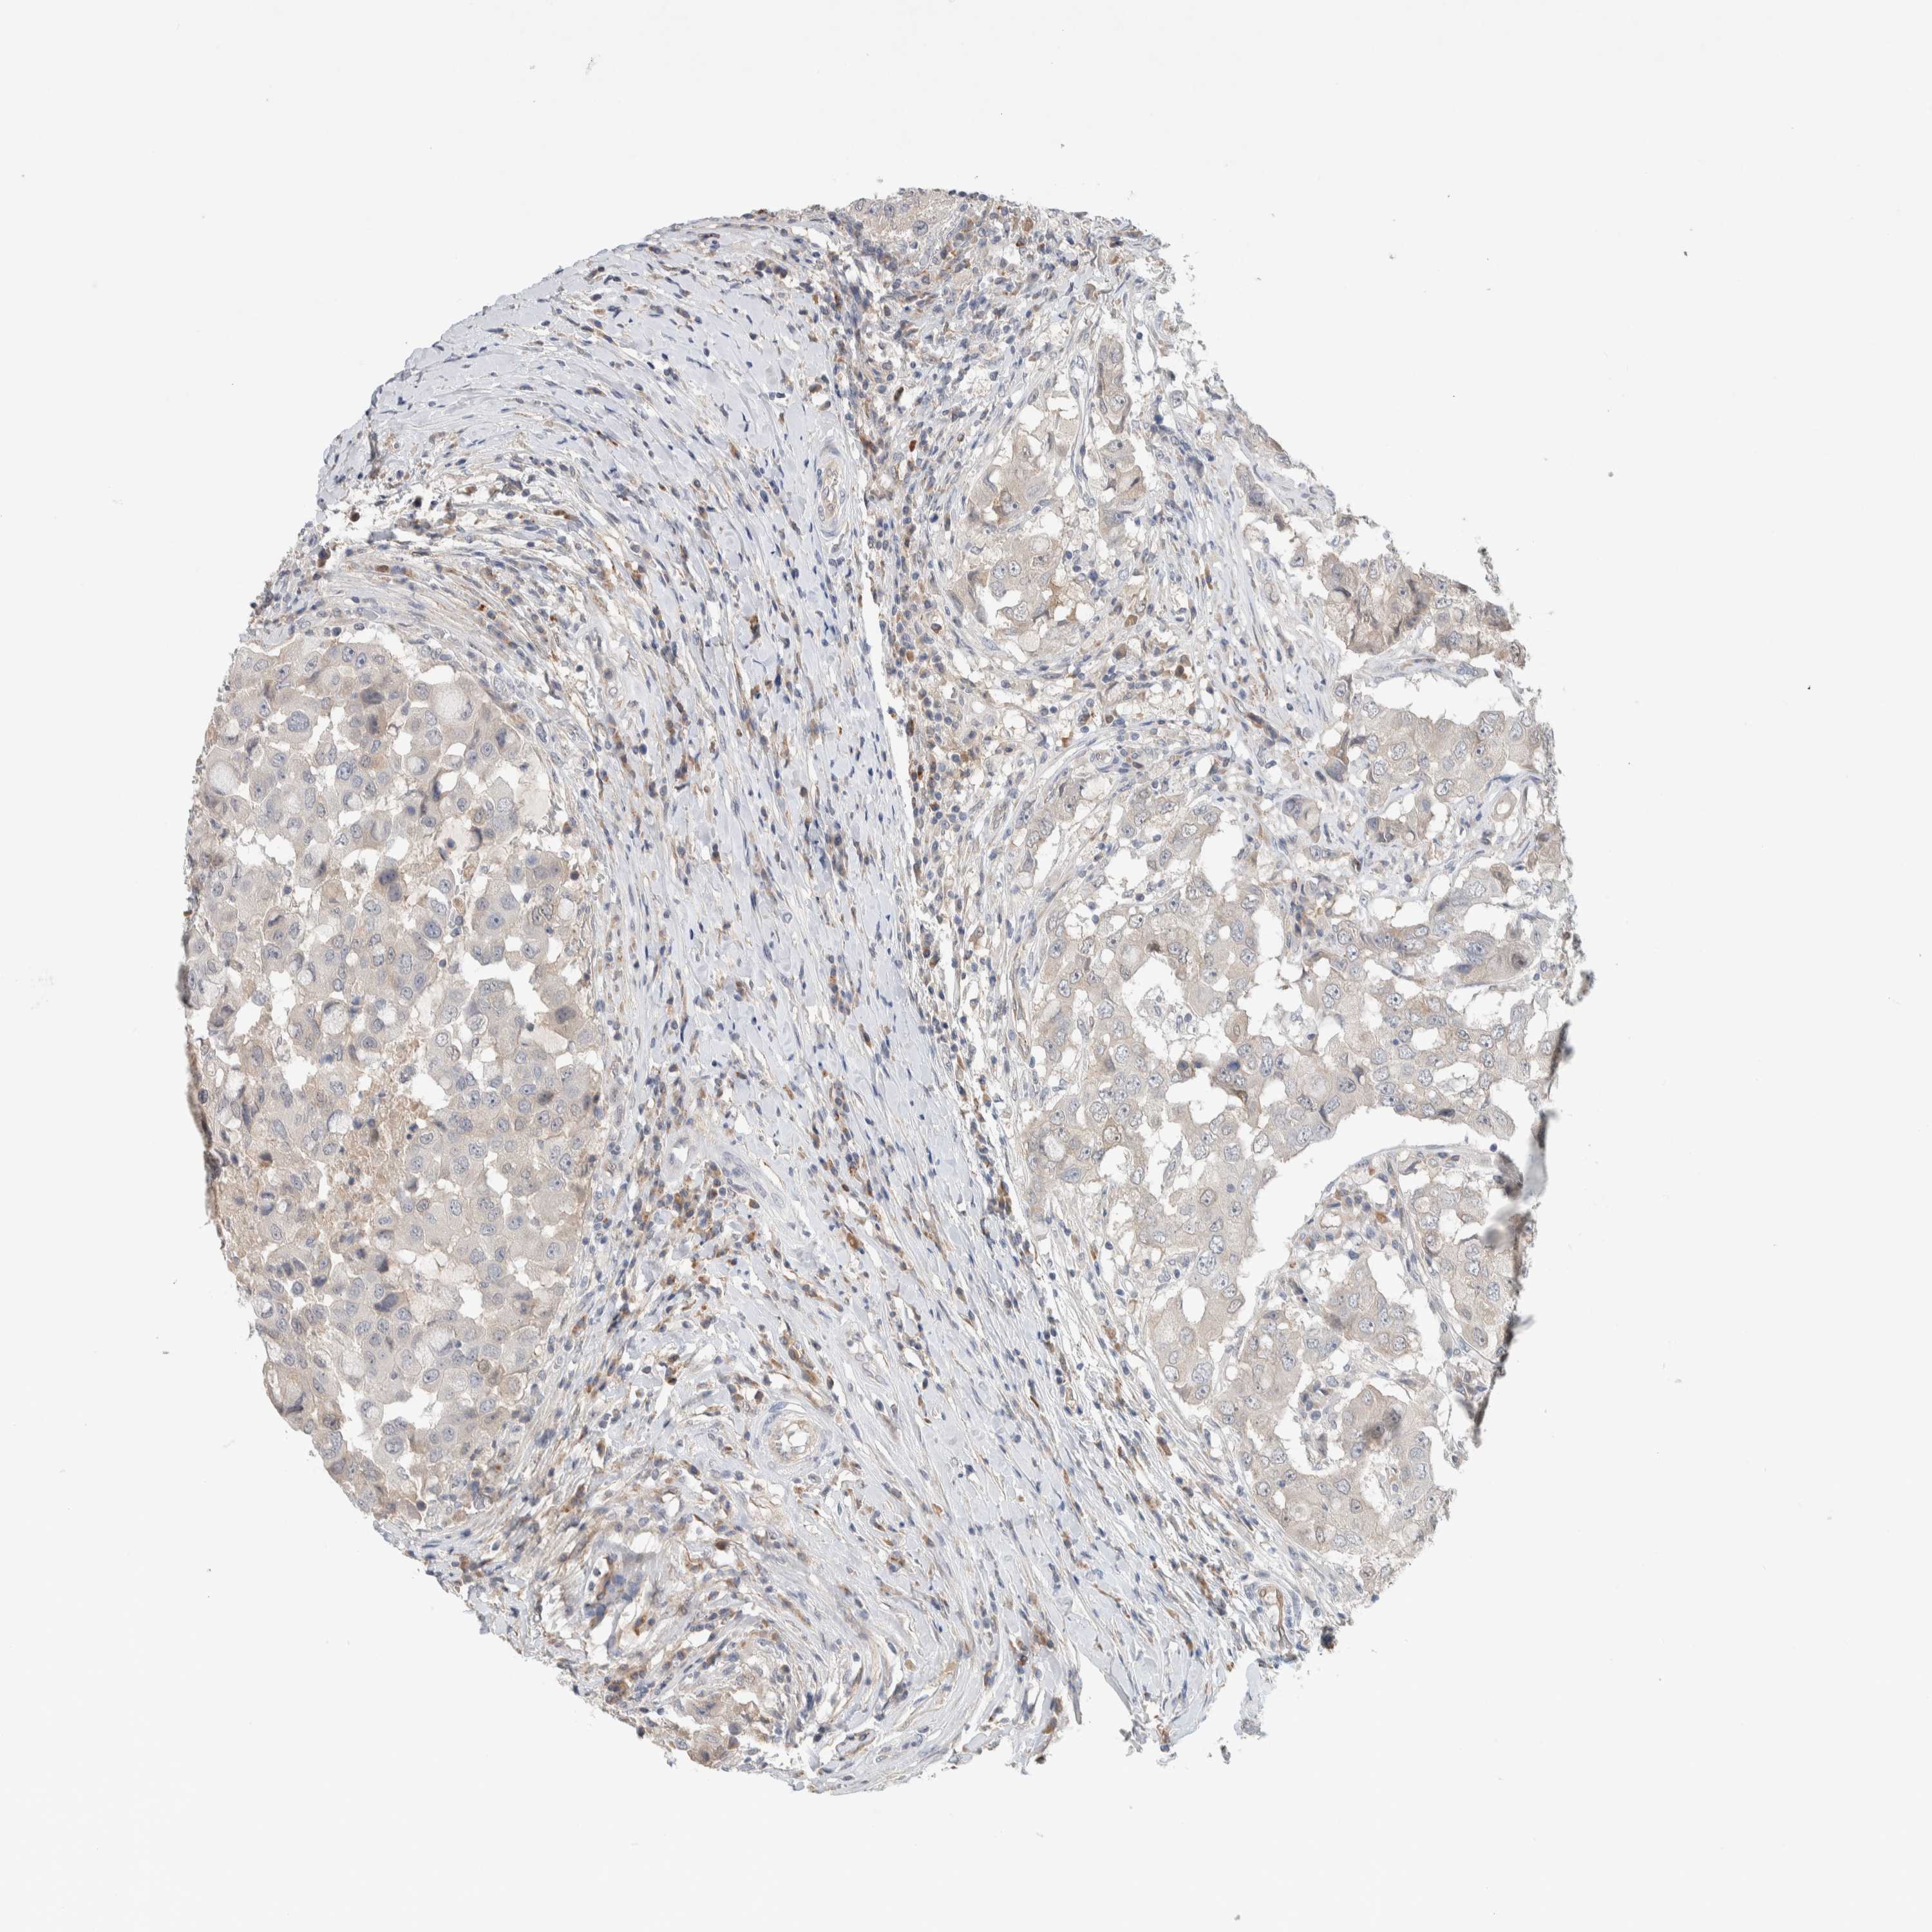

CANCER BREAST CANCER Show tissue menu

BRCA TCGA BRCA VALIDATION PROTEIN EXPRESSION